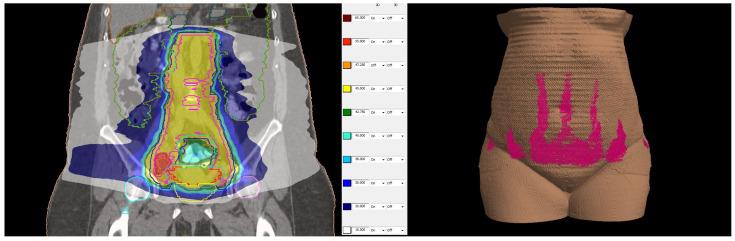

: The purpose of this report is to investigate the feasibility of combined modality treatment in a case of locally advanced cervical cancer in a patient with inherited epidermolysis bullosa as well as to suggest a protocol for cervical electronic brachytherapy. : The patient was treated with image-guided external beam radiotherapy and concomitant chemotherapy to a dose of 45 Gy in 25 fractions with a simultaneously integrated boost of 55 Gy in involved lymph nodes. The maximal skin dose was 34.09 Gy. Intracavitary electronic brachytherapy was applied to the uterine cervix in 4 fractions of 7 Gy and contributed no dose to the skin. : The treatment was tolerated well with no early toxicity. During the 3-month period of follow-up, no adverse events of grade 2 or higher were detected, and no exacerbation of skin lesions was noted. : This is the first report of treatment of cervical cancer in a patient with inherited epidermolysis bullosa where combined concurrent chemoradiotherapy and intracavitary electronic brachytherapy demonstrated feasibility and safety. The followed institutional protocol for treatment planning and delivery ensured low doses to organs and risk and reproducibility.

本报告的目的是探讨在一名患有遗传性大疱性表皮松解症的局部晚期宫颈癌患者中进行综合治疗的可行性,并提出一种宫颈电子近距离放疗方案。该患者接受了图像引导的外照射放疗和同步化疗,剂量为45 Gy,分25次进行,同时对受累淋巴结进行55 Gy的同步整合加量照射。最大皮肤剂量为34.09 Gy。对子宫颈进行了4次腔内电子近距离放疗,每次7 Gy,未对皮肤造成剂量。治疗耐受性良好,无早期毒性。在3个月的随访期间,未检测到2级或更高等级的不良事件,也未发现皮肤病变加重。这是首例关于遗传性大疱性表皮松解症患者宫颈癌治疗的报告,其中同步放化疗和腔内电子近距离放疗显示出可行性和安全性。后续的机构治疗计划和实施方案确保了对器官的低剂量、低风险和可重复性。